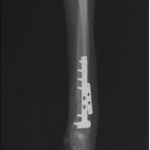

他院にて左大腿骨遠位の成長板骨折(salter-harrisⅠ型)が認められており、治療相談を目的として来院。当院にて、キルシュナーワイヤーを用いたピンニングにより骨折部位の整復を行いました。術後の経過は良好で、現在も経過観察中です。

術後レントゲン

Arthrex社のターゲティングデバイスを用いてピンニングの位置を調整することで、確実な固定を行っています。当院ではこの手術器具以外にも、人の手術にも使用される様々な器具を導入し、手術精度を高め、また医療メーカーと新しい器具の開発、試作にも取り組んでおります。